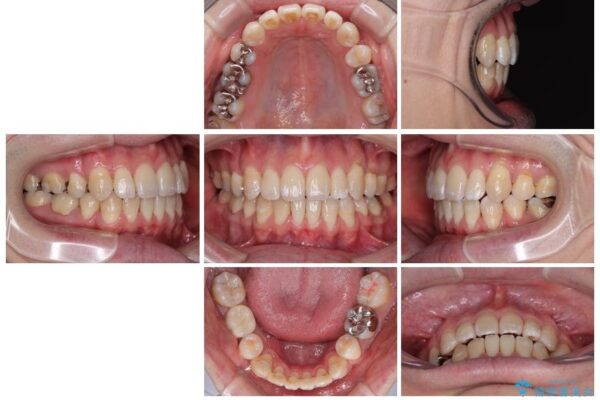

治療前

• 口元の突出感を改善!目立ちにくいワイヤー矯正で自信を持てる自然な横顔に 治療前画像

「横から見ると唇が前に出て見えるのが気になる…」 「マスクを外すのが恥ずかしい…」 そんな口元の突出感に悩まれてご来院された患者様。

精密検査の結果、上下左右の小臼歯4本を抜歯し、そのスペースに前歯を後方へ移動させる矯正治療をご提案しました。